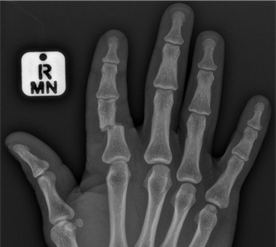

Imaging

X-ray is mandatory in clinically suspected fractures to confirm the diagnosis and define the fracture morphology to help decide on treatment. Occasionally CT scans are required in the case of complex fractures.